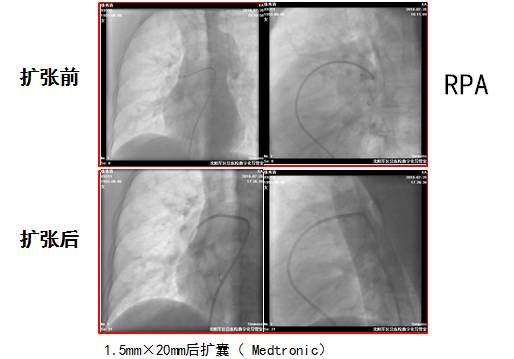

第1次扩张后肺动脉压力降低

肺动脉压力由术前152/48/83降至112/32/59mmHg

第2次肺动脉造影结果